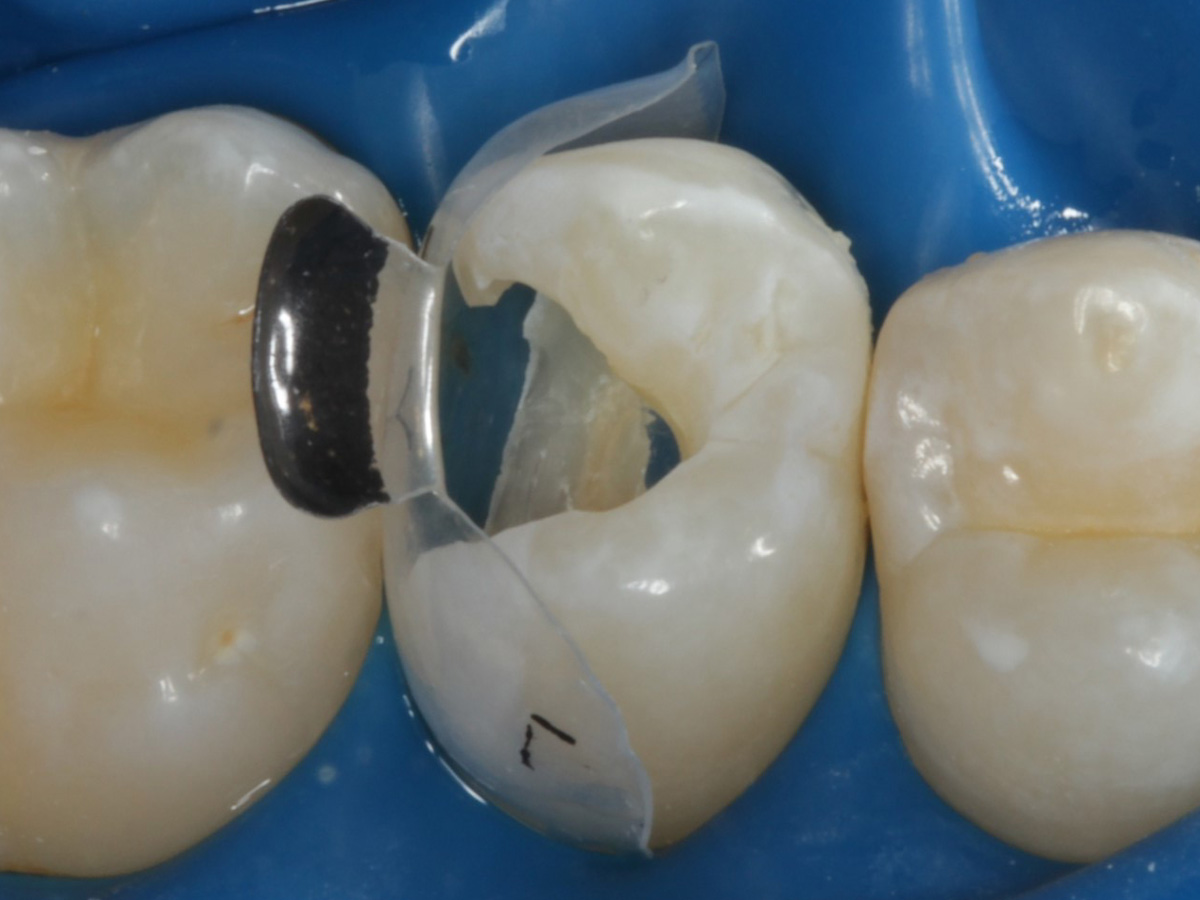

Abbildung 9

Nach Applikation der Matrize: Evolve Schwarz Prämolar- 7 mm; Schmelzätzung

Abbildung 10

Nach Spray und Trocknung der Kavität: perfekte Adaptation der Matrize insbesondere tief subgingival